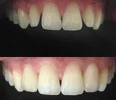

Laminate veneer